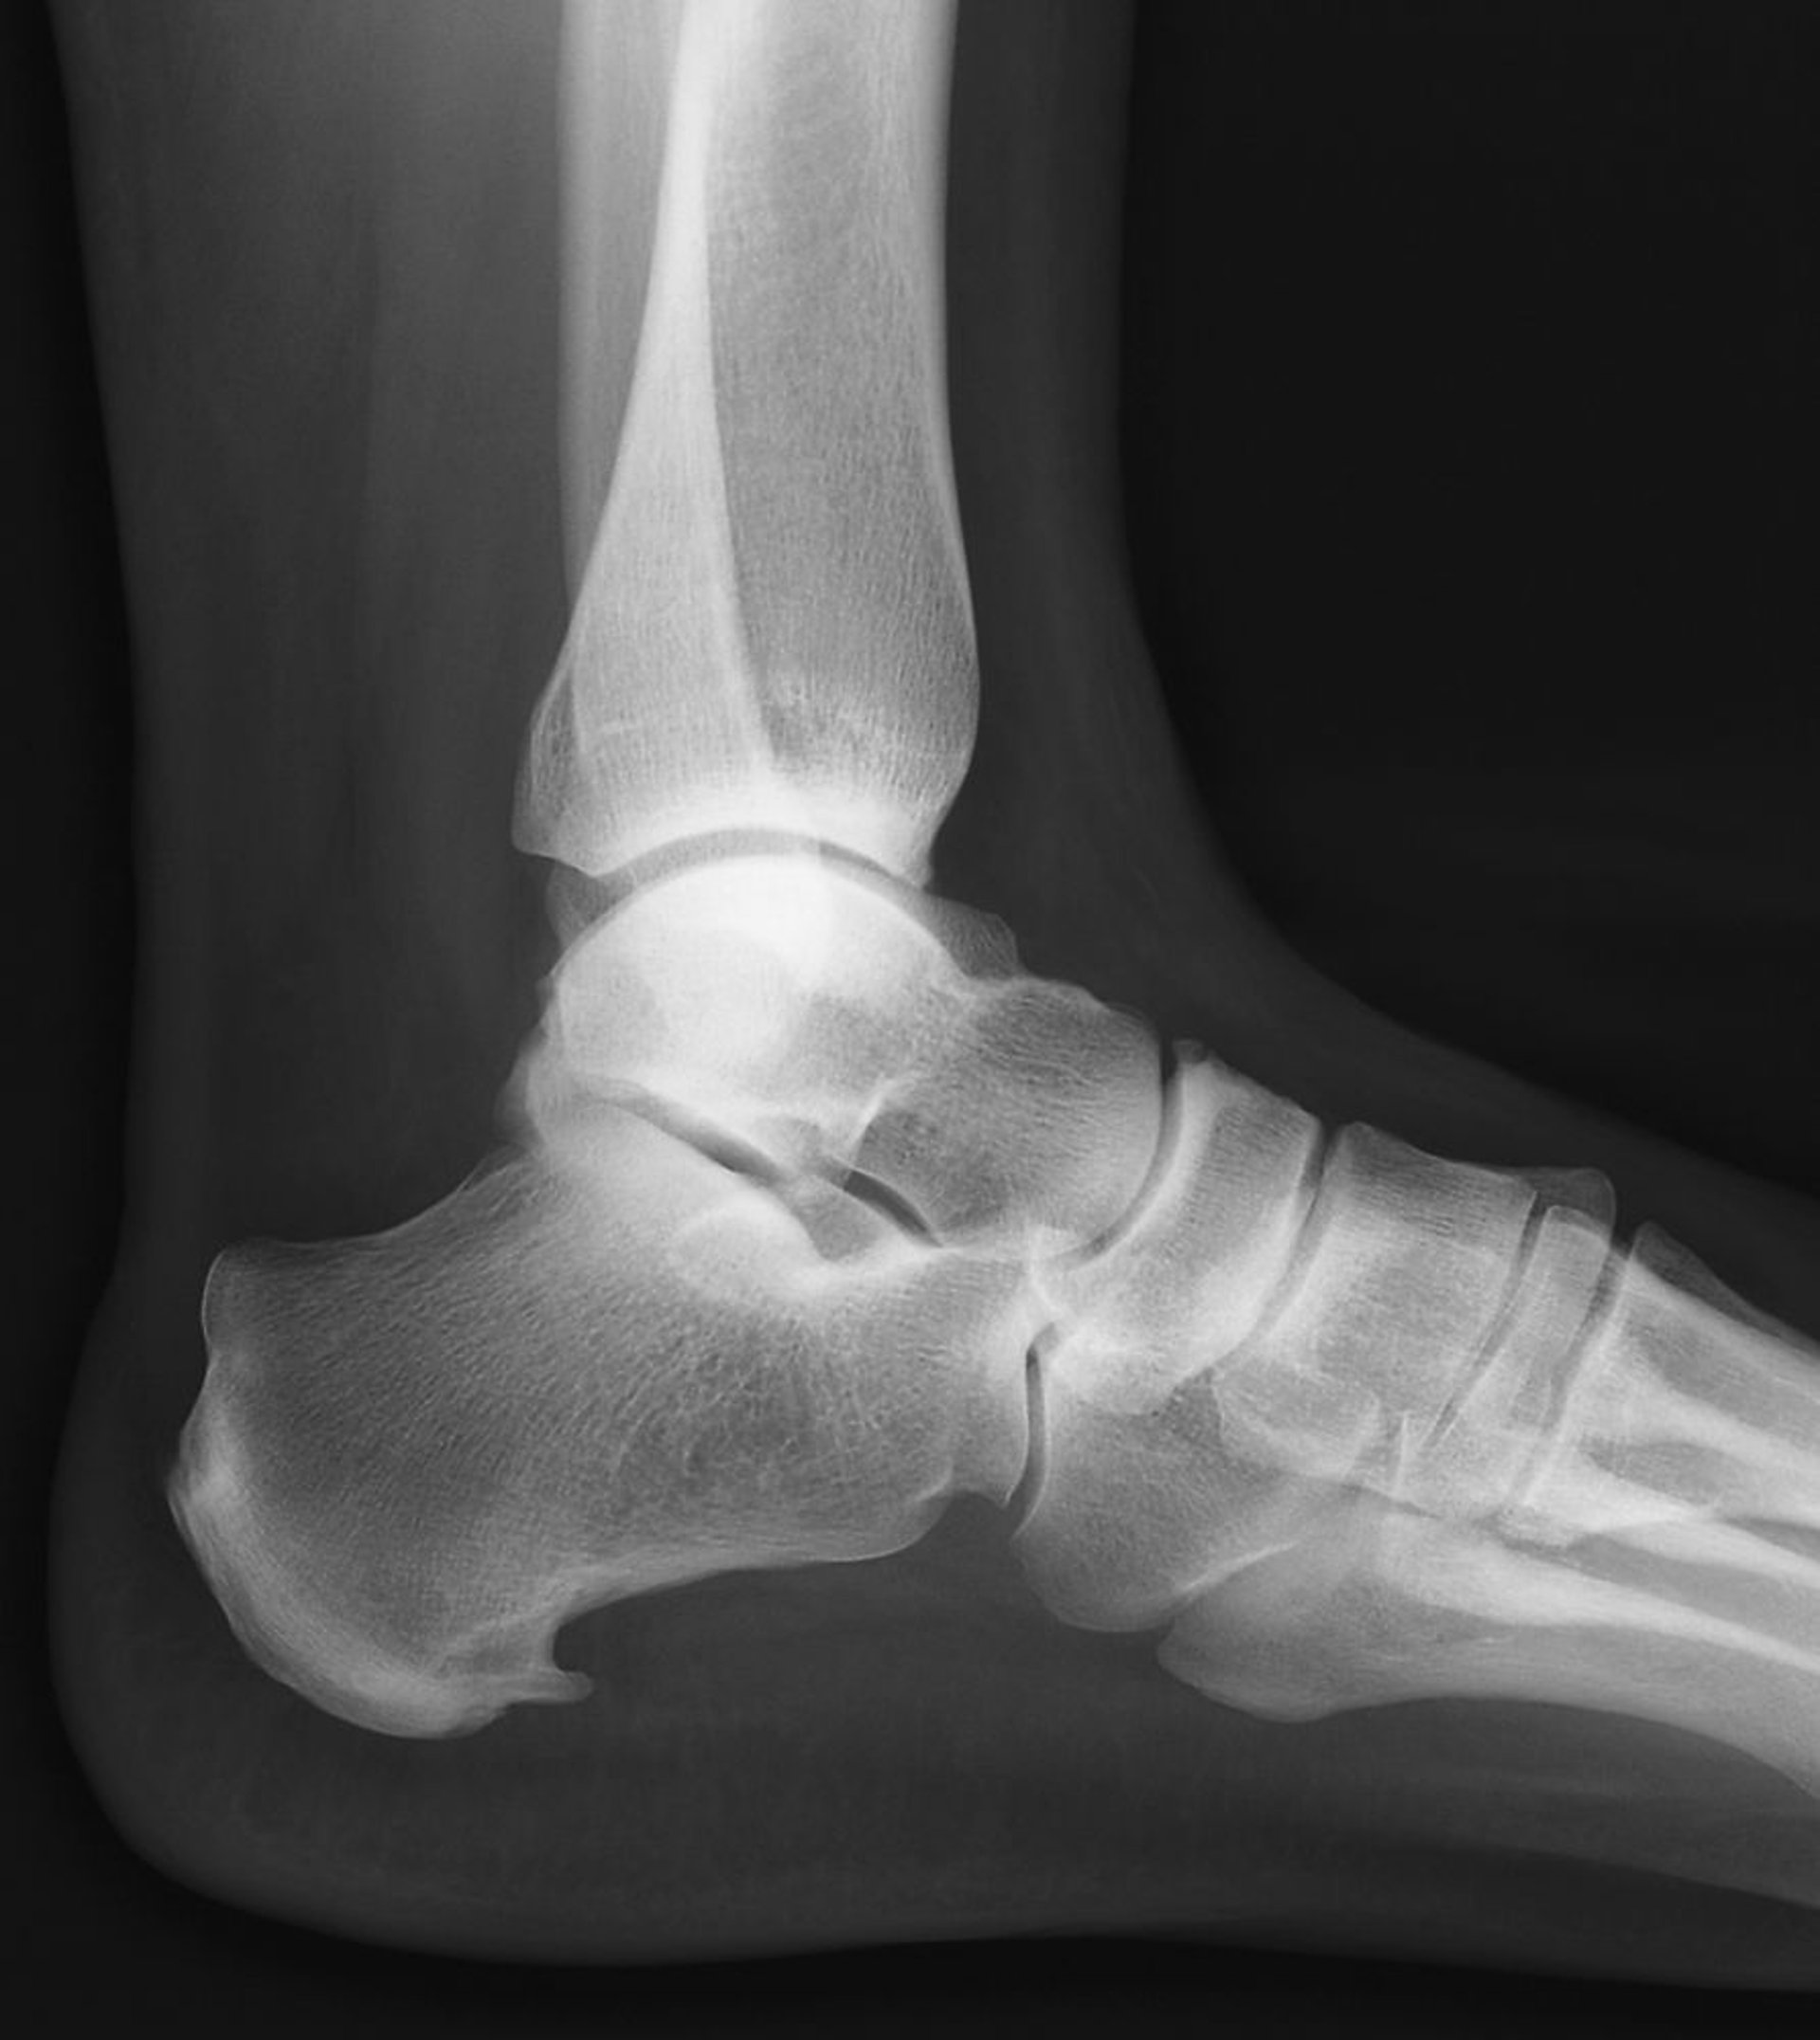

Epine calcanéenne

L'épine calcanéenne est une exostose osseuse qui s'étend vers l'avant en bas du calcanéum.